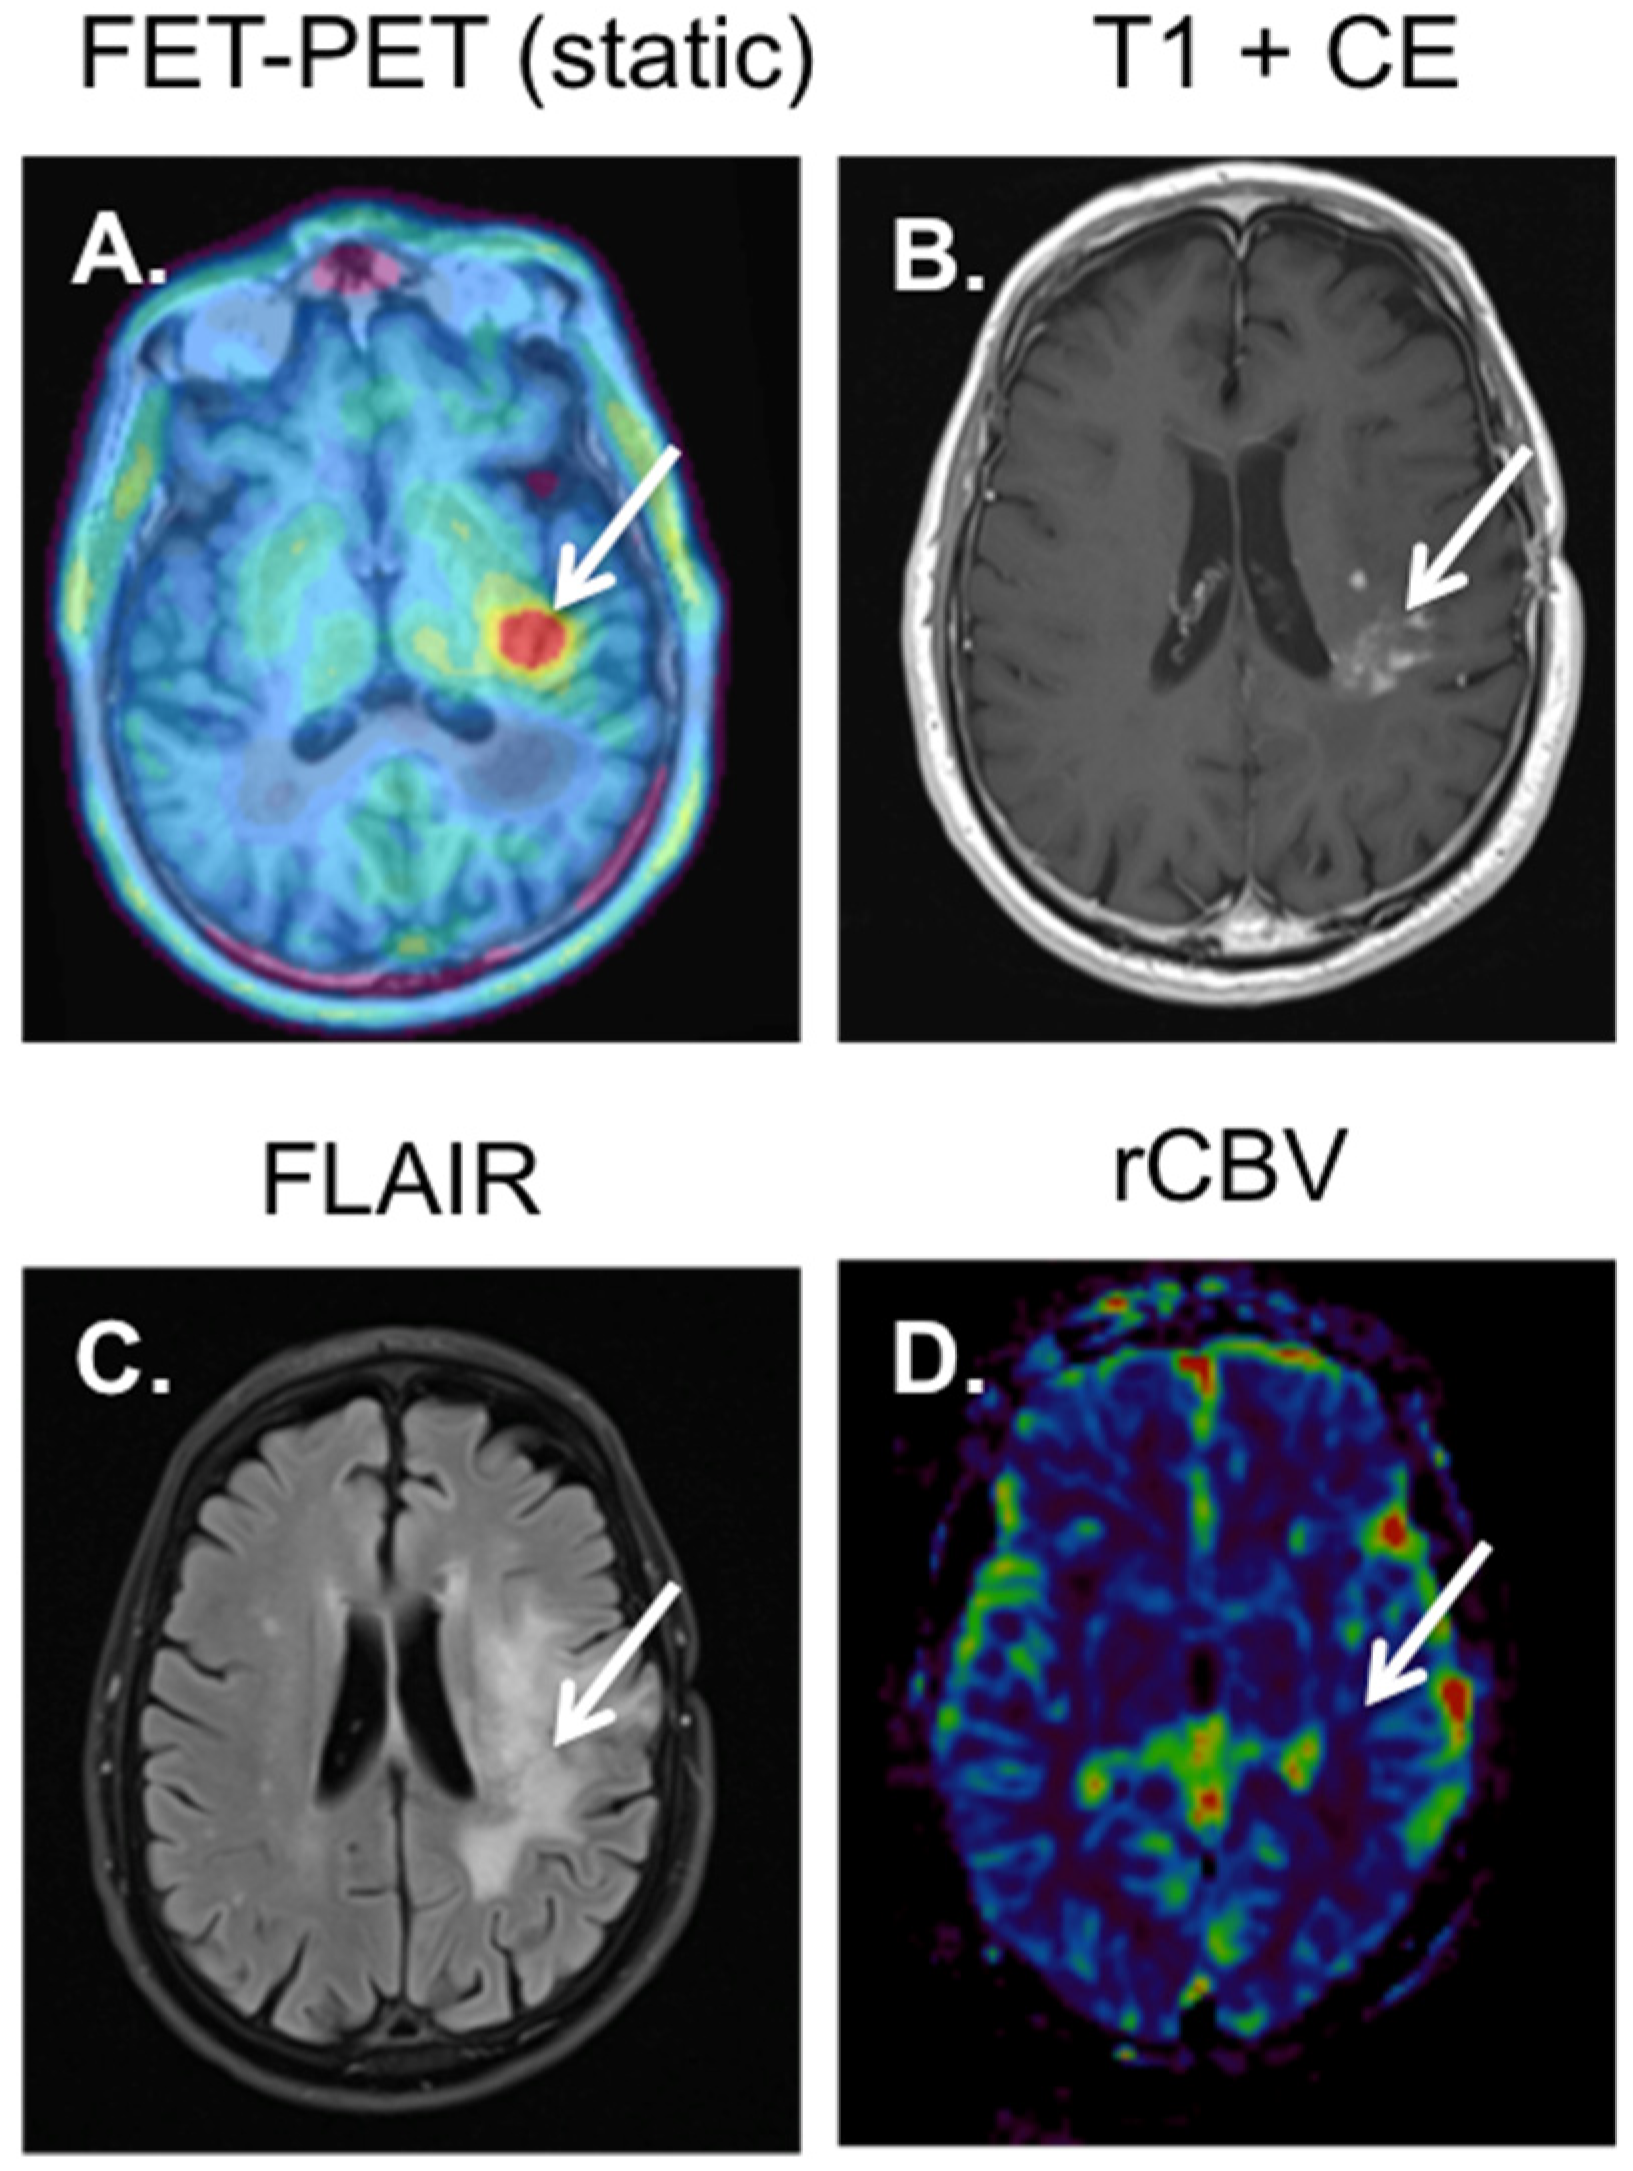

4. 18F-FET-PET-MRI